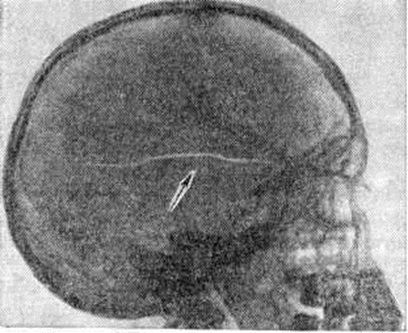

Основной рентгенологическое признак нарушения целости кости — линия Переломы Большое диагностическое значение имеет смещение отломков, наличие которого настолько бесспорно доказывает нарушение целости кости, что надобность в дифференциальной диагностике отпадает. Как бы подробно ни была описана рентгенологическое картина Переломы, наиболее полное и правильное представление о степени и характере смещения отломков врач может составить лишь при непосредственном просмотре снимков. Захождение отломков одного за другим при продольном смещении на рентгенограмме в одной проекции может сопровождаться наслоением теней концов отломков — так называемый суперпозицией теней. В этом случае точное определение смещения отломка возможно на основании данных снимков во второй проекции. При Переломы плоских костей (лопатка, ребра, таз и другие), при которых по техническим причинам производство снимка во второй проекции затруднено, суперпозиция отломков часто является единственным достоверным признаком Переломы Распознавание продольных смещений с расхождением отломков обычно не представляет каких либо затруднений. Подобного рода смещения наблюдаются при Переломы надколенника с разрывом связочного аппарата, локтевого отростка, вертелов бедра, отрывах костных выступов, к которым прикрепляются мышцы, сокращающиеся при повреждениях и приводящие к расхождению. Интерпозиция мягких тканей между отломками костей при рентгенологическое исследовании не распознается. Различные виды Переломы в наиболее информативных проекциях представлены на рисунок 4—11.

Если линия Переломы на снимке не достигает противоположного края кости, Переломы называют неполным, или трещиной. Начавшись у одного края кости и постепенно суживаясь, трещина исчезает в структуре неизменённого костного вещества. Чаще всего трещины возникают в плоских и губчатых костях, в первую очередь в костях черепа, пяточных костях; гораздо реже они встречаются при травмах трубчатых костей. Внутрисуставным считают Переломы, при котором нарушение целости кости распространяется на её суставной конец.

Наиболее часто за Переломы принимают апофизарные и эпифизарные ростковые хрящевые зоны, псевдоэпифизы (добавочные эпифизы), сосудистые каналы, добавочные косточки и зоны перестройки Лоозера (смотри полный свод знаний: Лоозера зона). Распознавание ростковых и хрящевых зон в отличие от Переломы основывается на знании сроков окостенения различных костей, учёте анамнестических и клинические, данных и большом опыте врача, производящего исследование. Дифференциально-диагностическим признаком Переломы в области ростковых зон служит более или менее выраженное смещение отломков, в частности ядра окостенения повреждённой стороны по сравнению со здоровой. Таковы же основы дифференциальной диагностики Переломы псевдоэпифиза. Часто за линию Переломы или трещину принимают сосудистые каналы (особенно для a. nutricia), имеющиеся почти в каждой кости и местами выделяющиеся на фоне коркового вещества, а также в костях черепа. О том, что это сосудистый канал, а не Переломы, говорят характерное расположение ровные контуры и прямолинейное направление достаточно широкого щелевидного просветления.Затруднения в дифференциальной диагностике Переломы может вызвать наличие добавочных и двойных сесамовидных костей стопы и кисти. В этих случаях полезным может оказаться исследование симметричной области, хотя подобного рода варианты развития скелета могут быть и односторонними. Добавочные косточки имеют всегда ровные чёткие округлые контуры, в то время как для Переломы характерны зазубренные, неровные контуры,, а при сопоставлении краёв отломков зазубренные контуры должны полностью совпадать и зубцы одной кости заполнять выемки другой. Внешнее сходство с линией Переломы на рентгенограмме имеют так называемый зоны перестройки Лоозера. В рентгеновском изображении такая зона представляется в виде узенькой полосы просветления, очень похожей на линии Переломы, особенно при наличии небольших периостальных наслоений на соответствующем уровне кости, симулирующих костную мозоль. Дифференциальная диагностика между истинным Переломы и зоной перестройки на основе одних рентгенологическое данных очень трудна. Диагностике помогают характерная для зон перестройки локализация (метатарзальные, большеберцовая кости, дистальный конец бедренной кости и другие) и отсутствие в анамнезе травмы, а также наличие дистрофических заболеваний и функциональный перегрузки отдельных костей или скелета в целом, которые могут обусловить появление зон перестройки Лоозера (рахит, болезнь Педжета и другие). Симметричные и множественные изменения всегда говорят в пользу зон перестройки.